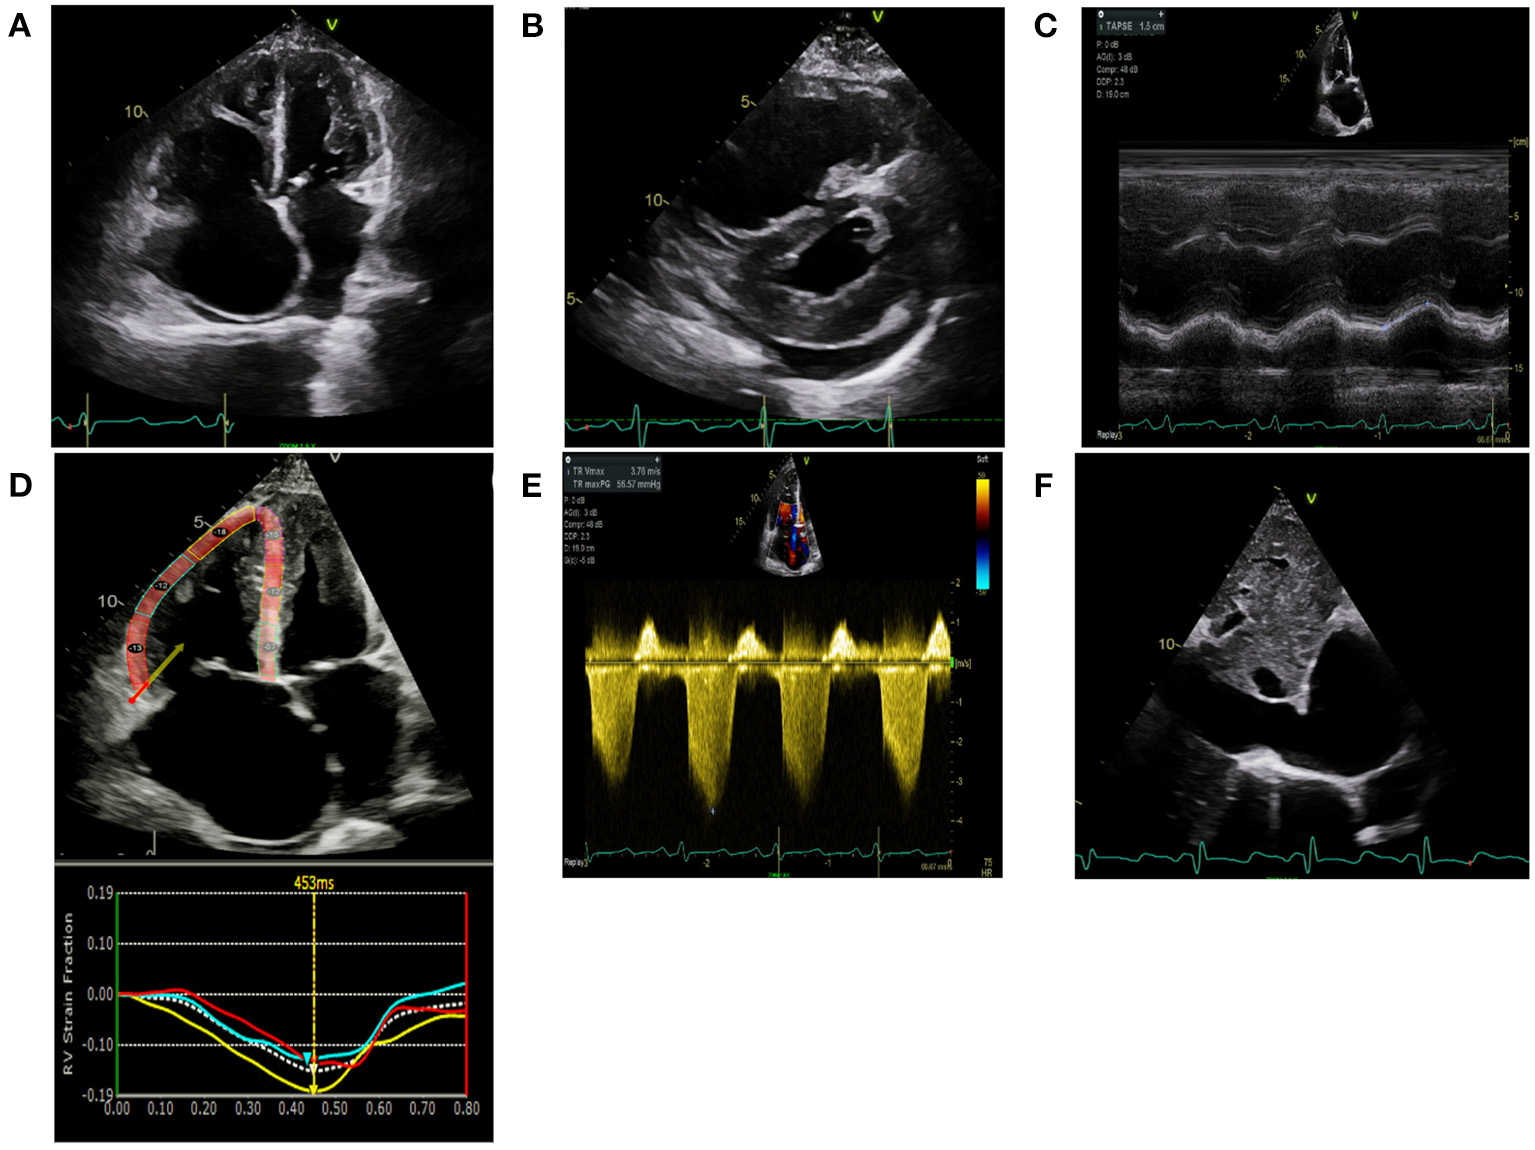

TTE is the most common imaging modality used to screen for PH and is the mainstay for screening, monitoring of therapeutic response, and prognostication (11). As most deaths from PH are from right heart failure, recognizing the presence, and quantifying the degree of right heart dysfunction, is helpful in monitoring disease progression and prognostication. In addition to conventional two-dimensional (2D) TTE, speckle-tracking strain imaging and three-dimensional (3D) echocardiography are more specialized techniques that are increasingly becoming part of the standard of care in monitoring right heart structure and function. Representative echocardiographic images are shown in Figure 1.

Figure 1

Echocardiographic images are shown in a scleroderma patient with severe pulmonary hypertension on stable therapies. (A) Apical 4 chamber view demonstrates severe right atrial enlargement with bowing of the interatrial septum from right to left suggestive of elevated right atrial pressures. The right ventricle is severely dilated and hypertrophied with a prominent moderator band. The left ventricle is hypertrophied and small. (B) Parasternal short-axis is shown in the same patient with marked RV enlargement and evidence of RV pressure overload distorting the normal circular short-axis geometry of the LV. There is a small posterior pericardial effusion present. (C) Tricuspid annular plane systolic excursion (TAPSE) utilizes M-mode techniques to measure the longitudinal motion of the basal right ventricular wall segment during systole as an estimate of right ventricular systolic function. TAPSE is mildly reduced at 1.5 cm (normal >1.6 cm) however fractional area change was 24% (moderate-severely reduced). (D) Right Ventricular Longitudinal Systolic Strain (RVLSS) is a recent echocardiographic advancement based on ultrasound-myocardial tissue interactions. Each segment of the RV in this example corresponds with a strain curve with the white dotted line representing an average of the segmental strain for the regional curves in this view. Regional RV free wall strain is reduced in the basal and midventricular wall segments with less reduction in the apical segment. Global strain is an average of the three RV free wall segments and is −14.3%. (E) Right Ventricular Systolic Pressure utilizes the peak tricuspid velocity to calculate the peak right ventricular systolic pressure using the modified Bernoulli equation. RVSP= [peak gradient (mmHg) = right atrial pressure + (4 × Peak velocity 2)]. In this example, RVSP = 57 mmHg + 15 mmHg = 72 mmHg. (F) Right atrial pressures are estimated from the IVC diameter made in subcostal view at end-expiration. In this example, the IVC is severely dilated at 3.2 cm with minimal respiratory variation suggestive of markedly elevated right atrial pressure of 15 mmHg.